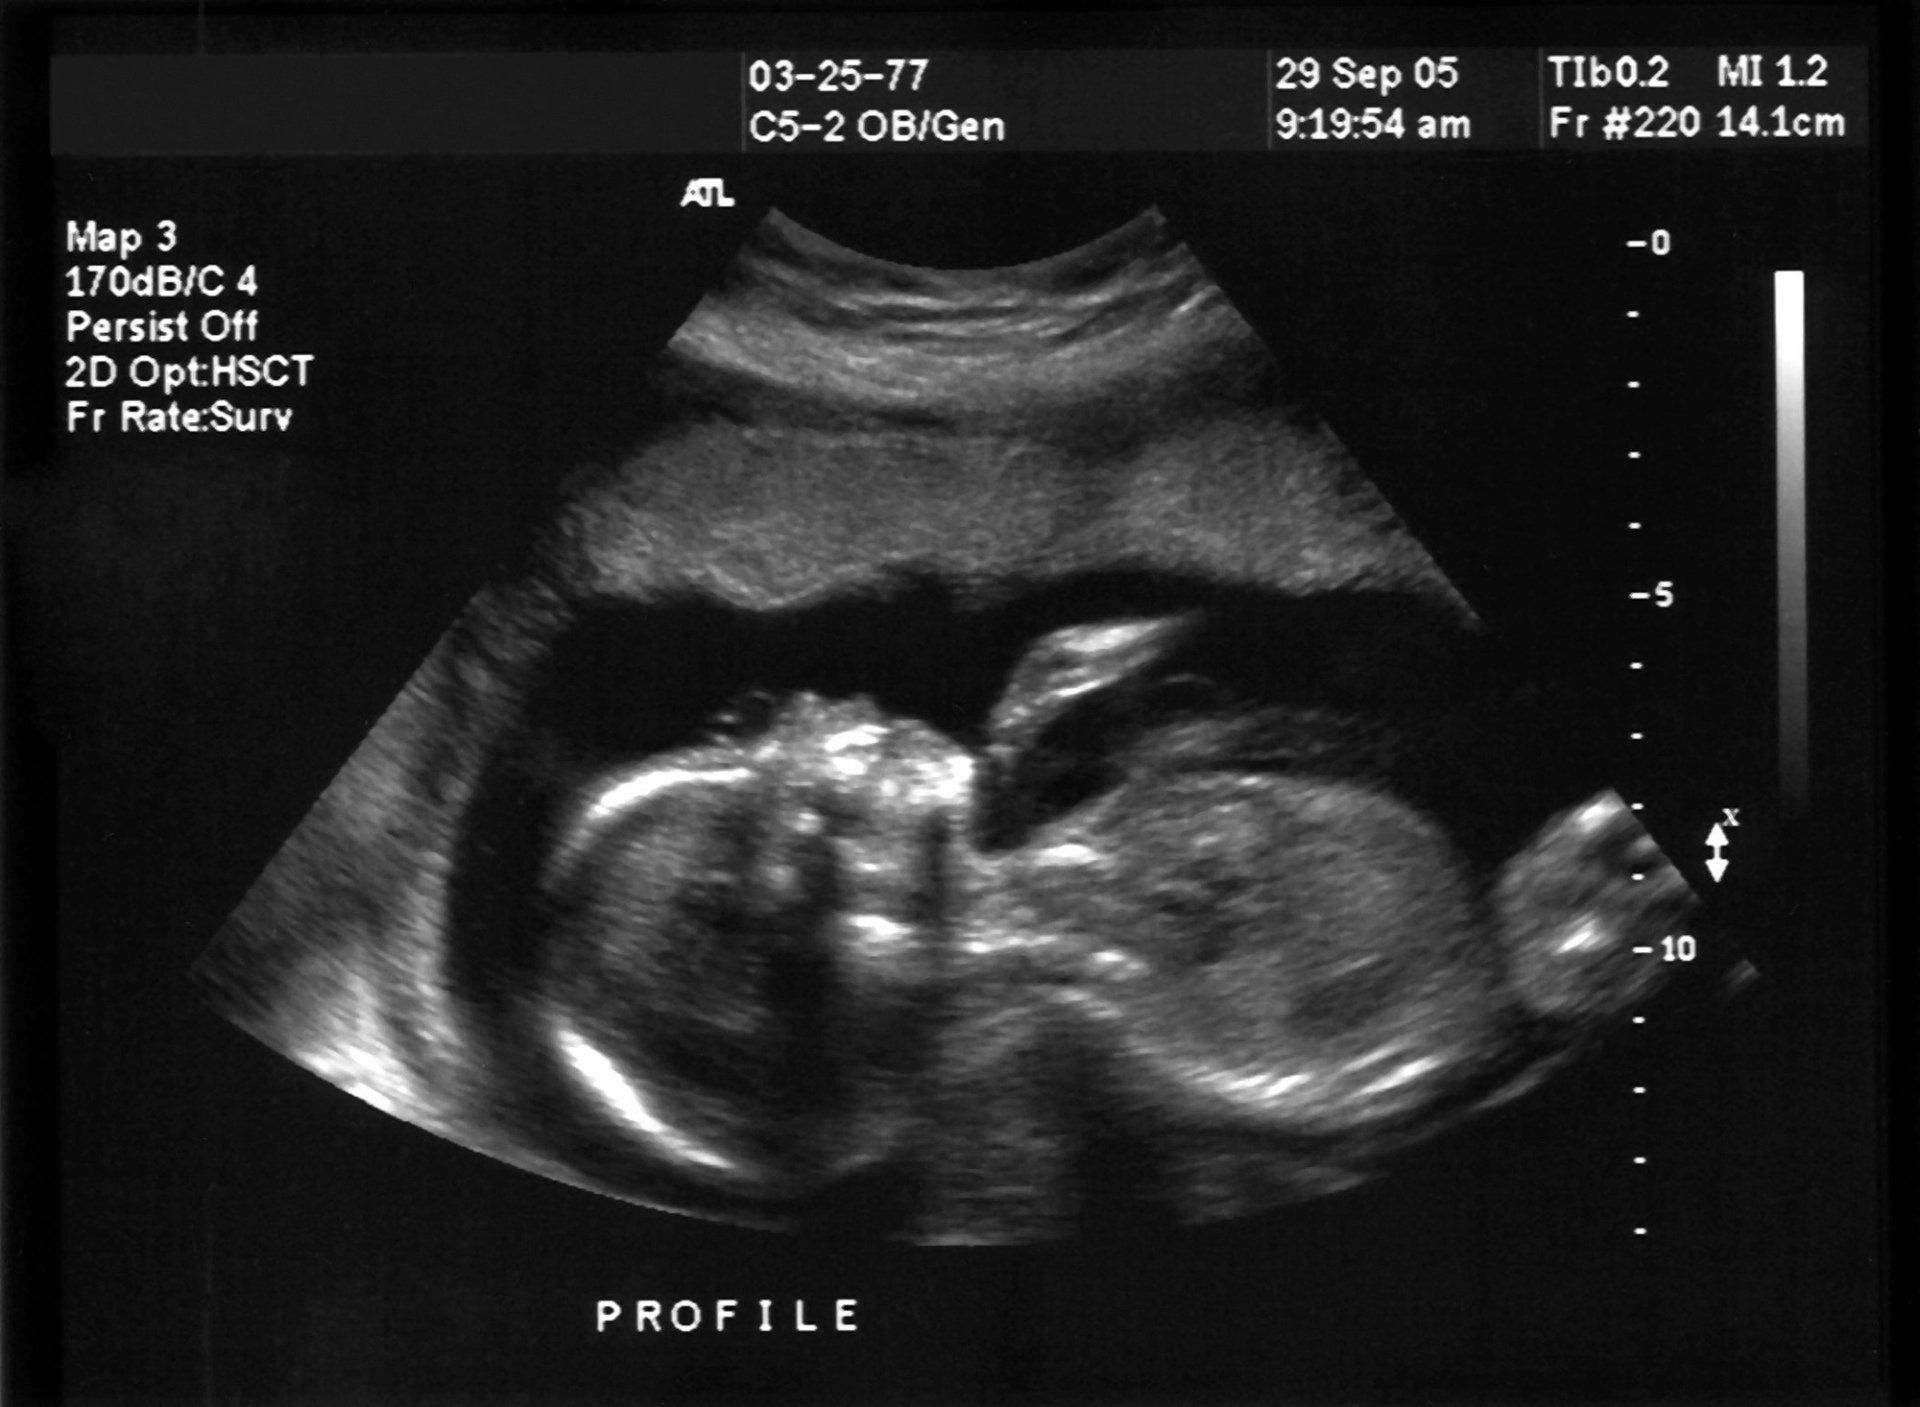

BIOMETRIA FETALE

Per biometria fetale si intende un'insieme di misurazioni ecografiche che vengono eseguite, dalla sesta alla tredicesima settimana di gestazione, da un ginecologo o da un'ecografista sul feto.

Lo studio del dott. Famiglietti, assiste le pazienti in dolce attesa per tutta la durata della gravidanze e ove fosse necessario esegue misurazioni ecografiche anche neonatali.